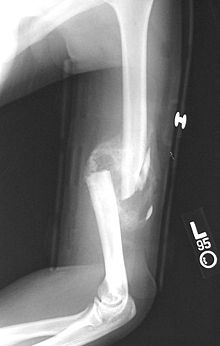

Comminuted midshaft humerus fracture with callus formation.

A fibrocartilage callus is a temporary formation of fibroblasts and chondroblasts which forms at the area of a bone fracture as the bone attempts to heal itself. The cells eventually dissipate and become dormant, lying in the resulting extracellular matrix that is the new bone. The callus is the first sign of union visible on x-rays, usually 3 weeks after the fracture. Callus formation is slower in adults than in children, and in cortical bones than in cancellous bones.[1]